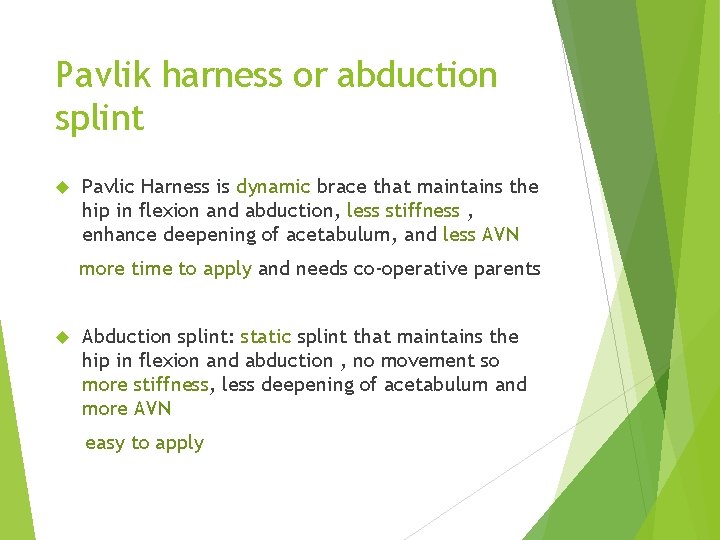

Pavlik harness or abduction splint Pavlic Harness is dynamic brace that maintains the hip in flexion and abduction, less stiffness , enhance deepening of acetabulum, and less AVN more time to apply and needs co-operative parents Abduction splint: static splint that maintains the hip in flexion and abduction , no movement so more stiffness, less deepening of acetabulum and more AVN easy to apply